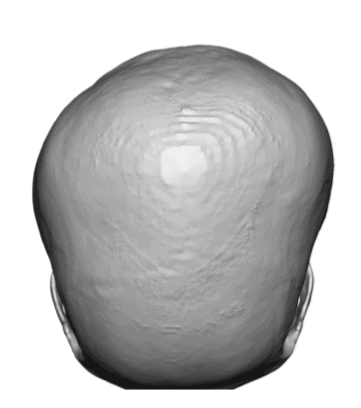

Desire for a higher and more prominent crown of the skull.

Crown of skull augmentation using a custom skull implant.

Desire for a higher and more prominent crown of the skull.

Crown of skull augmentation using a custom skull implant.